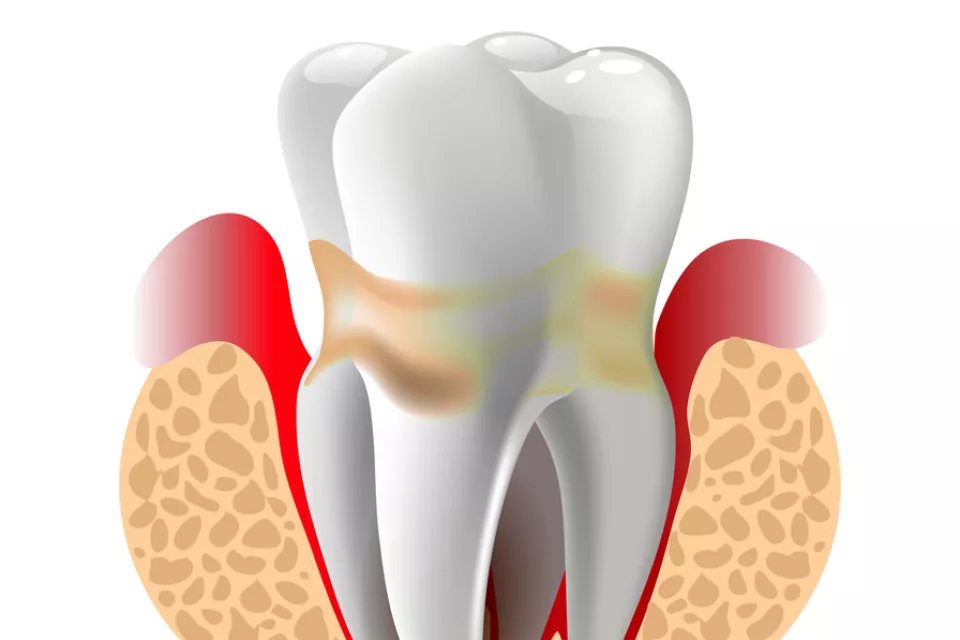

Úvodní léčba je konzervativní – zahájena hygienickou fází. Zahajuje se instruktáží správné zubní hygieny, odstraněním zubního kamene nad a pod dásní strojově – ultrazvukem nebo speciálními nástroji – kyretami.

Úvodní léčba je konzervativní – zahájena hygienickou fází. Zahajuje se instruktáží správné zubní hygieny, odstraněním zubního kamene nad a pod dásní strojově – ultrazvukem nebo speciálními nástroji – kyretami.